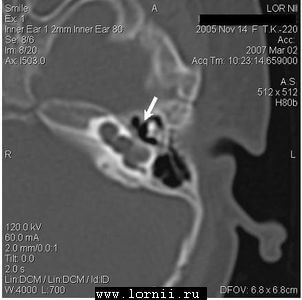

КТ височных костей выявила наличие двухсторонней аномалии развития улитки в виде неполного разделения I типа (табл. 4). При этом данное утверждение верно как для левого, так и для правого уха, несмотря на различную, на первый взгляд, картину (рис.1).

После обследования пациентке проведена КИ на левом ухе классическим доступом через антромастоидотомию и заднюю тимпанотомию, с введением электрода через кохлеостому. Для операции использовался специальный укороченный электрод (Med-El, Австрия), имеющий рабочую длину активного электрода около 12 мм, специально разработанный для применения в случаях аномалии или оссификации улитки.